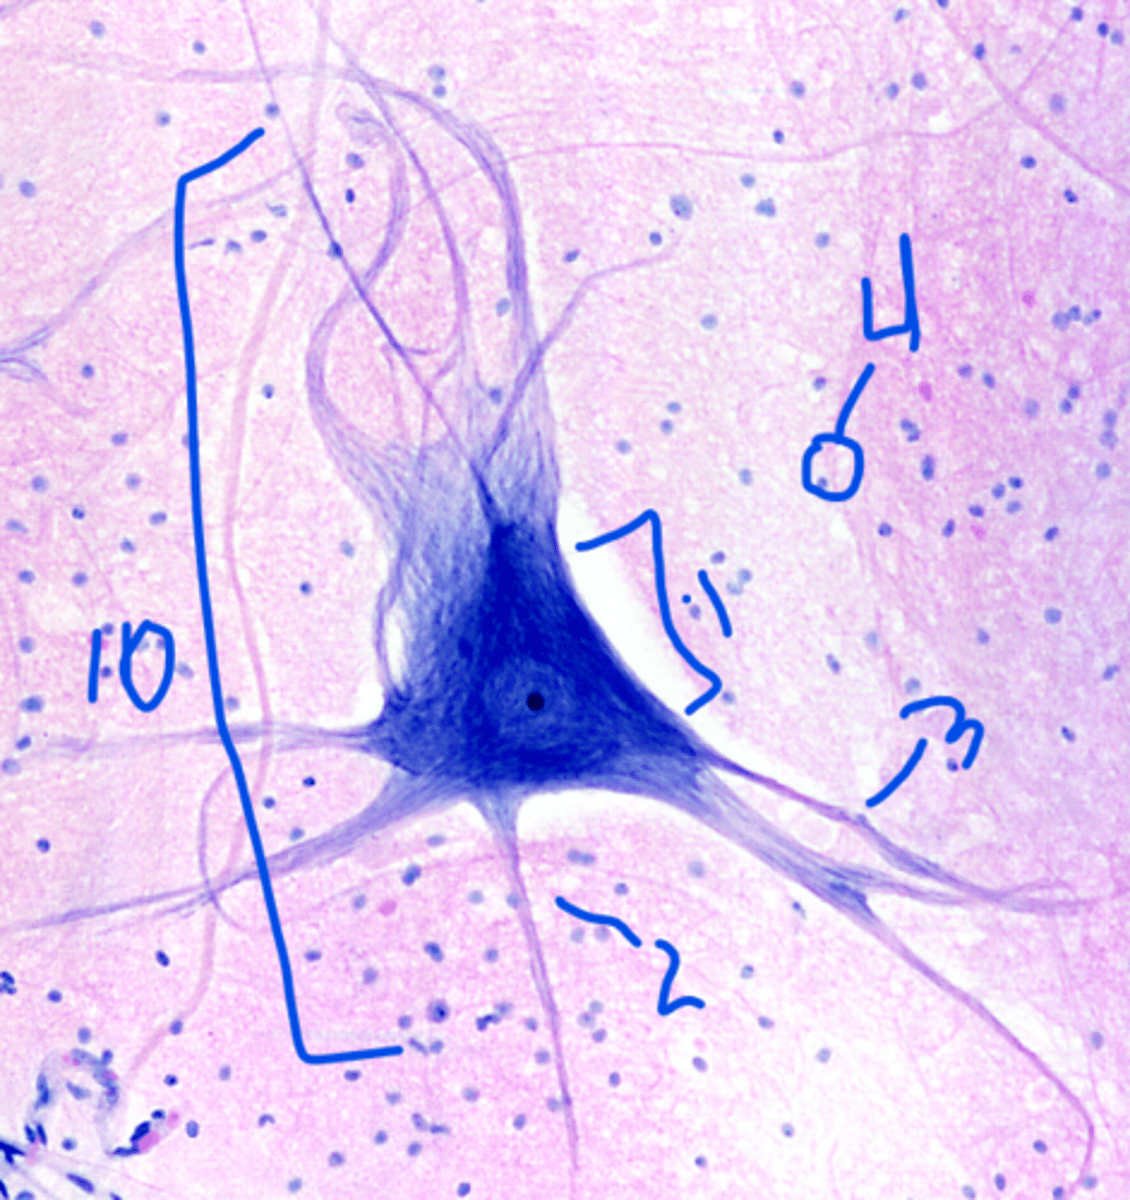

neuron

10

Neurosoma

1

axon

2

dendrites

3

neuroglia cell

4

dendrite